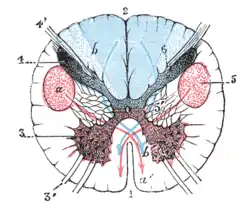

Section of the medulla oblongata through the lower part of the decussation of the pyramids.

the blue arrow, b, b’, indicates the course which the sensory fibers take. | |